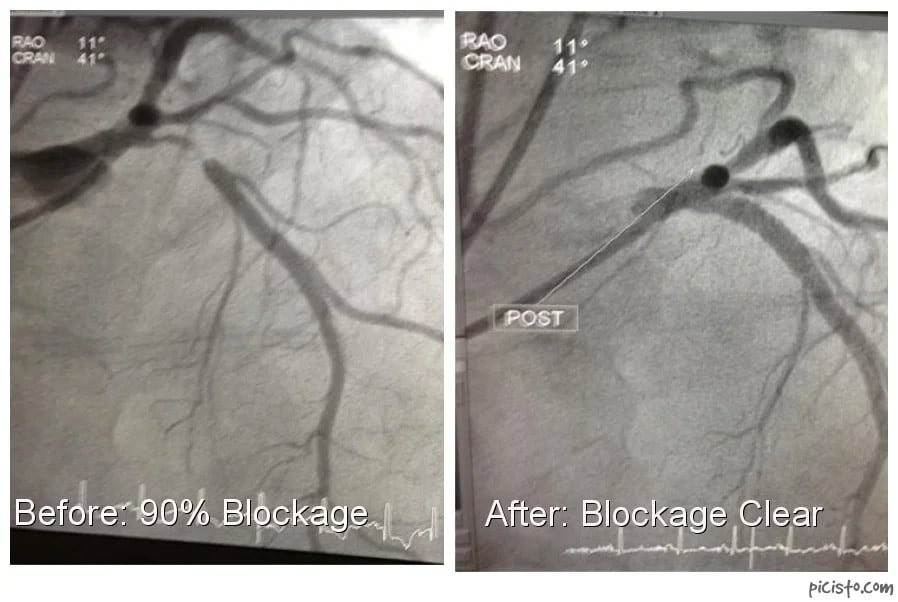

Today we are taking you inside a real case at Oklahoma Heart Institute. A patient in his 80s presented to the Emergency Room with an acute myocardial infarction (MI). He was a former smoker with no previous coronary disease. Angiography was performed which revealed a 90 percent blockage in a major artery, the Proximal left anterior desending (LAD) artery.

The after picture shows the artery is once again fully clear of any blockage.